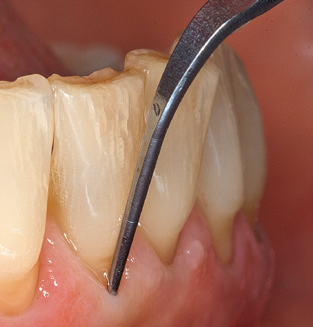

The current working concept for SPT

Updating the patient’s medical history is an important aspect of SPT and should occur at least once per year. It helps the dental team to identify and document any new risk factors. Especially when a patient is treated over many years, it is important to establish whether patient-specific and general health risk factors have changed. This primarily concerns a heightened risk as a result of diabetes, but other general conditions (cardiovascular disease and neoplasia) can also produce a modified risk profile as a result of the treatment performed and medication administered. Accordingly, updating the medical history as part of SPT is very important, as a modified risk profile may trigger the need to adapt the treatment interval. In the next step, it is important to afford the diagnostics due attention. Whilst instruments are a central aspect of SPT, findings and their documentation must never be neglected. The periodontological findings are essential for a good diagnosis; increases in the pocket depths and the BOP index are clear indicators of advancing periodontal and peri-implant disease. As such, the team should not shy away from probing implants too, with the aim of gathering the requisite data. At the same time, it is important to use periodontal probes with millimetre markings. Metallic probes have already been used for determining pocket depths around natural teeth for decades. In the case of implants, the challenge of recording correct and reproducible pockets depths is even greater. As the discrepancy between the implant diameter and the contour of the superstructure regularly results in overcontouring of the superstructure, flexible probes which still feature millimetre markings are a sensible solution for measuring pocket depths around implants (e.g., Colorvue Kit PCV11KIT6, Hu­Friedy; Fig. 4).

Fig. 4: Flexible probes with millimetre markings are recommended for the probing of dental implants (e.g. Colorvue Kit PCV11KIT6, Hu­Friedy). – Fig. 5a and b: A straight working tip (1P, W&H Dentalwerk Bürmoos GmbH) is a suitable instrument for use on all natural teeth. – Fig. 6: Curved working tips (3Pr/3Pl, W&H Dentalwerk Bürmoos GmbH) lend themselves to the processing of difficult-to-reach areas of the tooth and root surfaces (e.g. furcations). – Fig. 7: The tapered, hexagonal implant cleaning tip (1I, W&H Dentalwerk Bürmoos GmbH) permits atraumatic and efficient cleaning of the crown and abutment surfaces. – Fig. 8: Titanium and carbon curettes are suitable instruments for the manual cleaning of the implant surfaces.